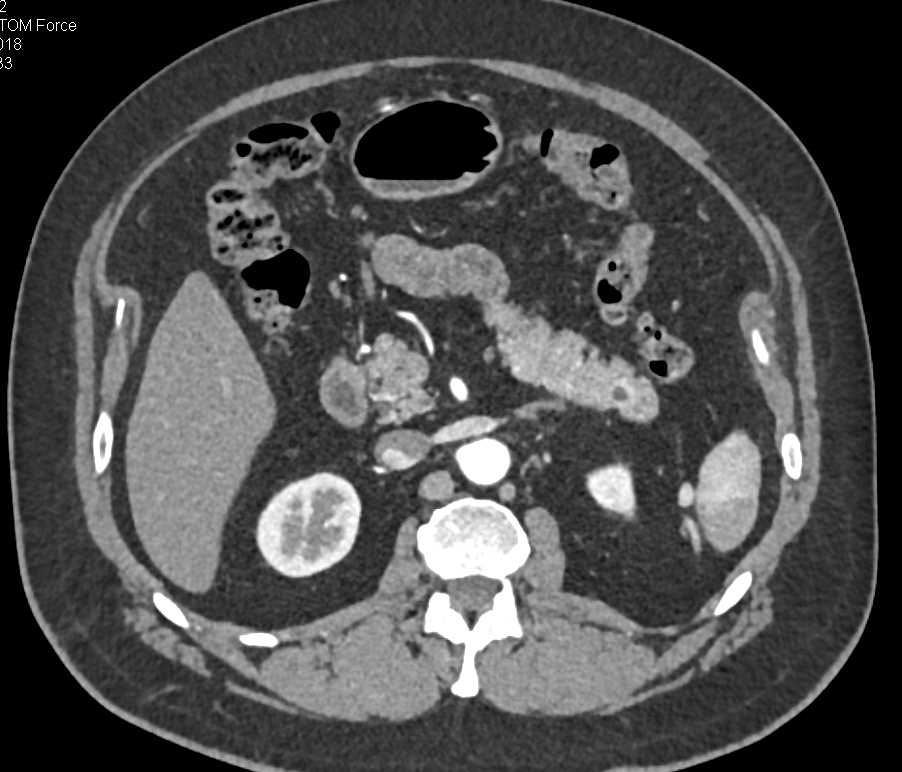

Polypoid Bladder Cancer and Calcified Right Adrenal Gland